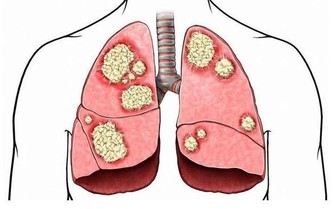

*****3.夜宵、早餐太油膩*****不少人喜歡深夜擼串、吃泡麵,早餐也愛吃油條之類的食物。日復一日,肝臟可受不了。脂肪的分解、代謝,少不了肝臟的參與。所以,油膩的食物會給肝臟帶來不小的負擔。如果脂肪攝入過多,來不及代謝,就會在肝臟堆積,形成脂肪肝。